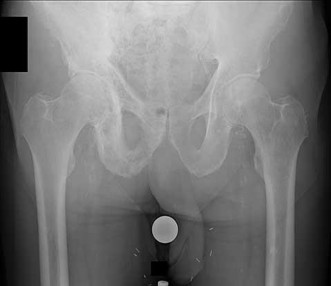

Question 1:

A 12-year-old obese boy presents with vague left thigh and knee pain. He is diagnosed with a Slipped Capital Femoral Epiphysis (SCFE) as seen in similar clinical scenarios. During percutaneous in-situ fixation, unrecognized penetration of the guide wire into the hip joint occurs. What is the most likely specific complication resulting from this technical error?

Correct Answer: Chondrolysis

Explanation:

Chondrolysis is a severe complication of SCFE characterized by rapid destruction of the articular cartilage. While it can occur idiopathically, its most established iatrogenic cause is unrecognized intra-articular hardware penetration. The 'approach-withdraw' fluoroscopic technique is required during pinning to assure pins are entirely intraosseous. Avascular necrosis (AVN) is usually due to damage to the epiphyseal blood supply (retinacular vessels) secondary to the initial displacement, forceful closed reduction, or posterosuperior pin placement.